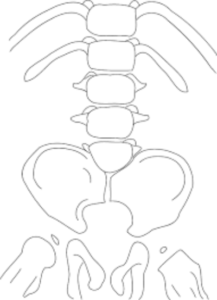

إذ يؤثر في التكوين الطبيعي للنصف السفلي (الذيلي) من الجسم؛ أي لا يتكوّن طبيعيًا جزء من العمود الفقري والنخاع الشوكي.

عدم انتظام عظام العمود الفقري السفلي

يمكن أن تكون عظام أسفل العمود الفقري مشوهة أو مفقودة؛ مما يعكس تأثيرًا سلبيًا في النخاع الشوكي كذلك.

إغلاق غير كامل في قاعدة العمود الفقري

قد تكون الفقرات (العظام حول النخاع الشوكي) مفقودة أيضًا؛ إذ تنتهي تلك الفقرات في كيس مغطى بالجلد مملوءًا بالسوائل.

يقع ذلك الكيس في الظهر جنبًا إلى جنب مع وجود بقع سميكة من الجلد في قاعدة العمود الفقري.

الجنف

من ضمن أعراض متلازمة التراجع الذيلي، إصابة العمود الفقري بالجنف (Scoliosis) أو الانحناء غير الطبيعي، ويؤثر ذلك في بنية الصدر مسببًا مشكلات التنفس.

عظام غير منتظمة في الأجزاء السفلية من الجسم

تظهر أعراض متلازمة التراجع الذيلي في الأجزاء السفلية من الجسم في صورة:

- أفخاذ أصغر حجمًا وأرداف مسطحة.

- احتمالية تكوّن عظام ساق غير منتظمة الشكل؛ إذ قد تظهر الركبة عند المصابين في وضع جانبي، أو تبدو الأقدام مشيرة إلى الجهة الخلفية أو الأمامية.